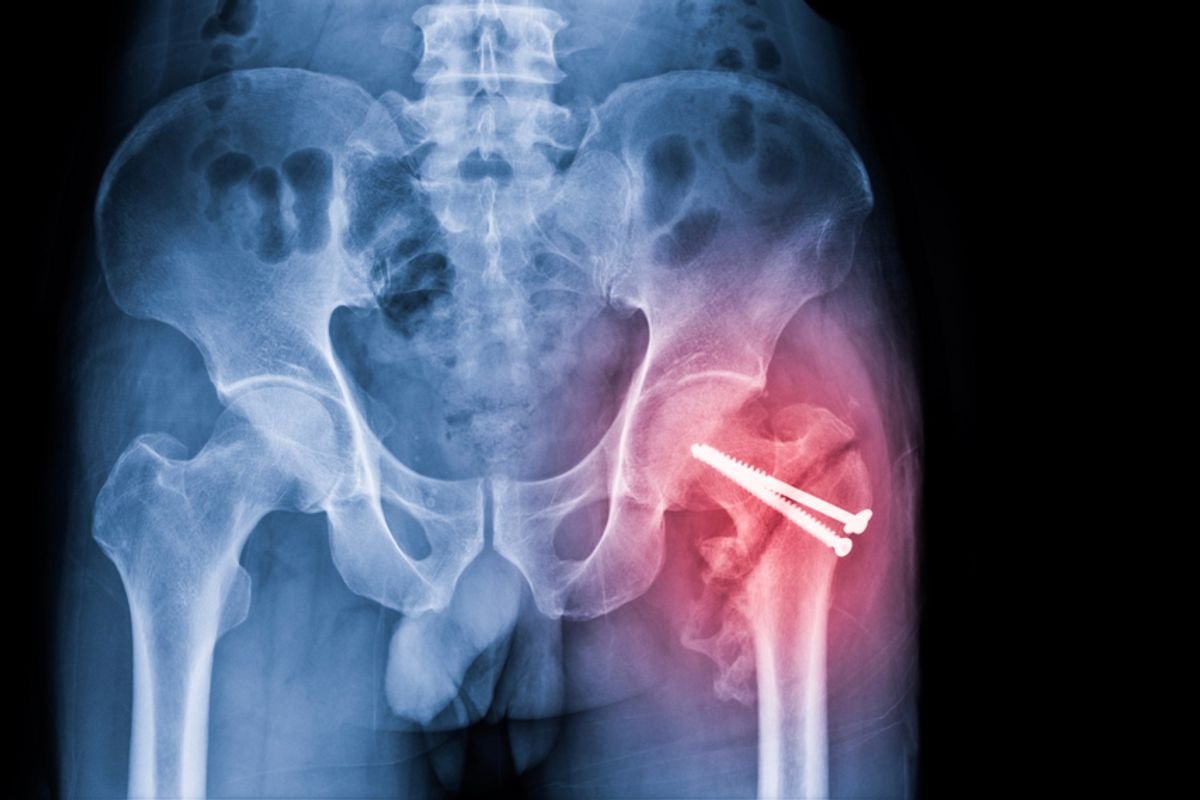

Hip Fractures Can Signal More Than a Broken Bone in the Elderly — Sometimes with Fatal Consequences

Hip fractures, though they may sound innocuous, are not as simple as a broken bone. Elderly patients can face a plethora of health issues following surgical treatments, with even death as a potential risk following the injury itself or post-operative complications.

But while accidental falls are a common reason someone might fracture their hip, even something as simple as getting up or walking could result in an injury. Those types of fractures, Chansky added, are pathological, meaning they occur in bone that is abnormal and structurally weak — a bone weakened by osteoporosis or cancer, for example, takes much less energy to break than a bone without either.

These underlying factors are why fracturing a hip is comparatively more dangerous than breaking an arm or leg, for example.

In older adults, immobility and bed rest can be especially dangerous because many of these complications can stem from this. Operating on the injury within 24 to 36 hours of the initial injury is important, though getting them up and moving after surgery is just as crucial.